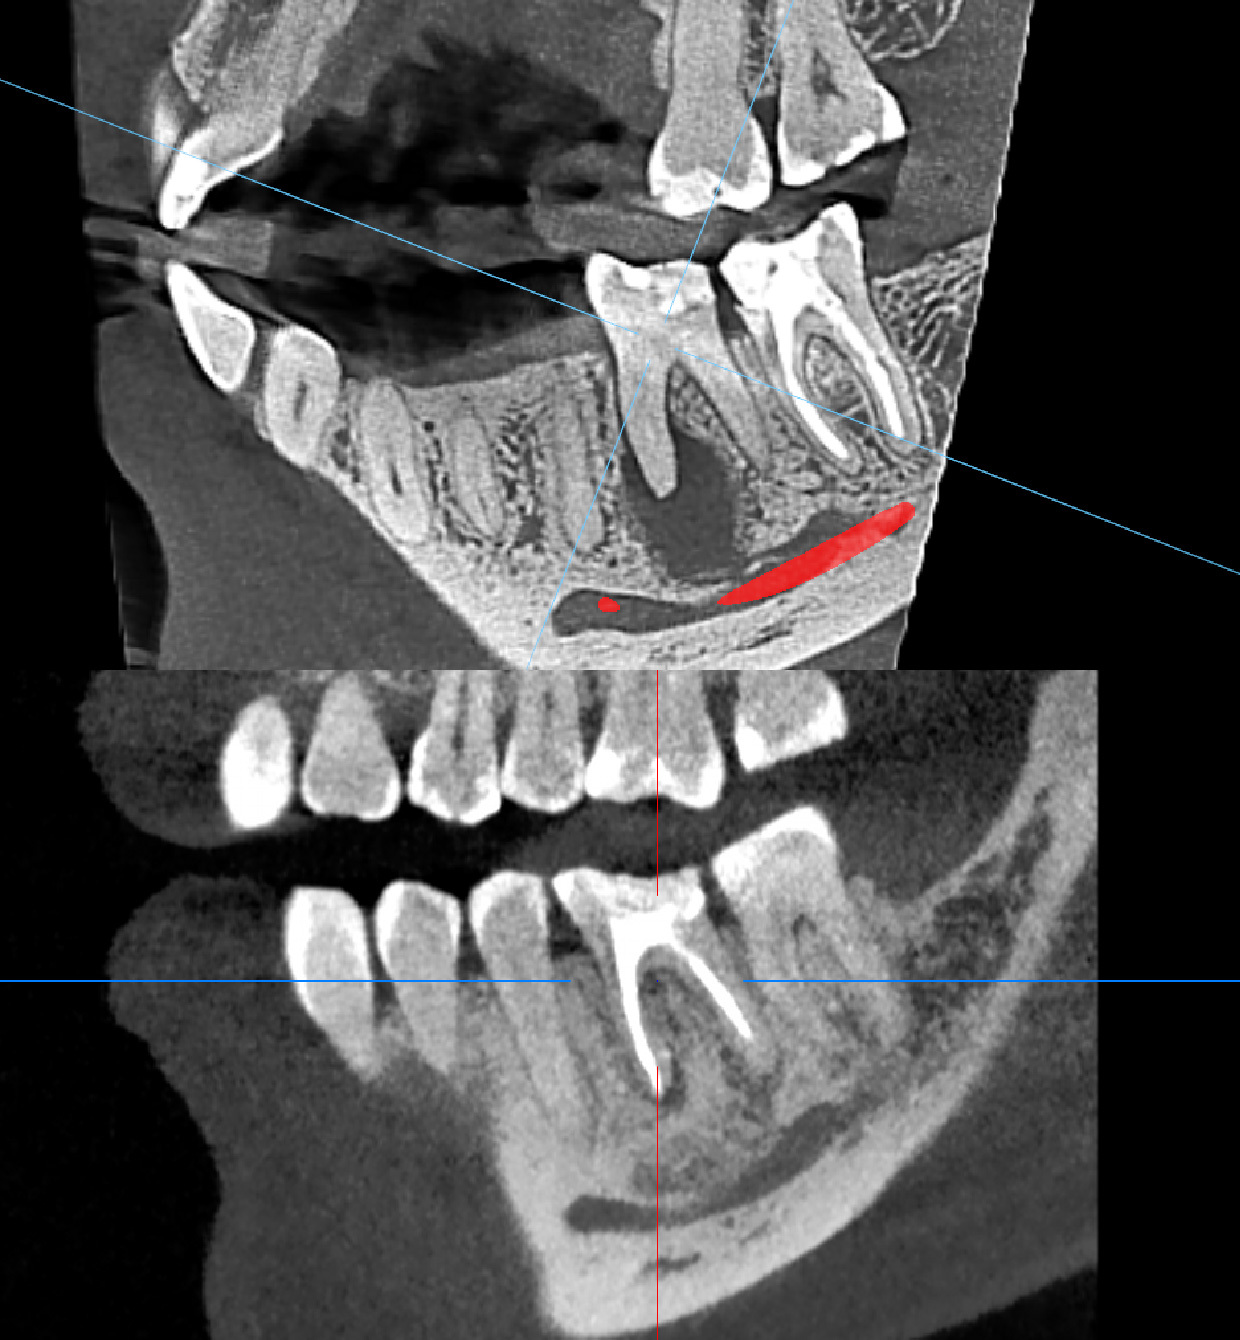

Как это часто бывает, пациенты не предъявляют жалобы при таких диагнозах. Так и в данном случае, пациента ничего не беспокоило. Кисту мы обнаружили на компьютерной томографии, которую сделали в профилактических целях.

Внешне: нарушение краевого прилегания пломбы, это когда она "отклеивается" от стенки зуба и видна как желтая полоска между пломбой и зубом, а также кариозное пятно на передней поверхности. Исходя из объема пломбировочного материала, врач сразу подозревает, что ранее зуб лечился в корневых каналах, а такие зубы требуют динамического контроля и покрытия коронками. Поэтому мы начали со снимка, на котором обнаружили большую кисту.

Лечение заключается в том, что корневые каналы освобождаются от старого материала, закладывается лекарство и выдерживается там несколько недель. Далее пломбируется обычным способом. И оставляется на динамическое наблюдение на 6-12 месяцев.

Через год мы сделали повторную компьютерную томографию и увидели положительный результат. Очаг инфекции ликвидирован, а кость в этом месте отлично восстановилась.